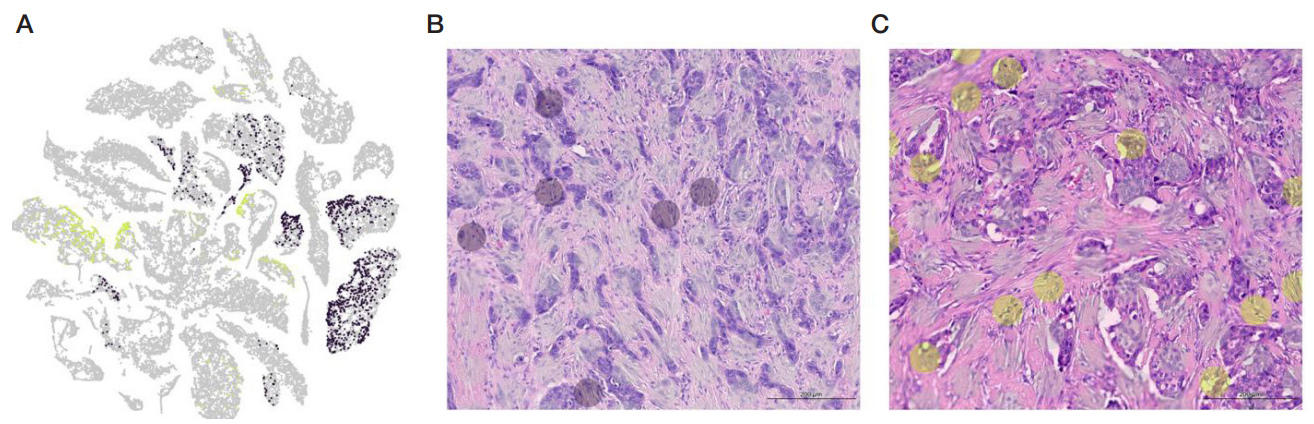

Transcriptomic features of FAP+ cells across molecular subtypes of breast cancer